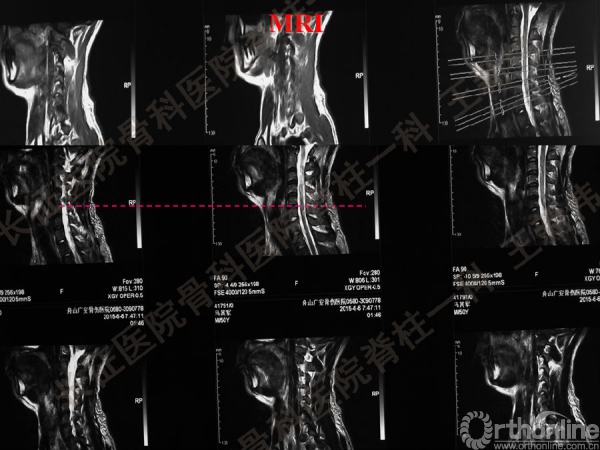

王新伟:颈椎后路通道下手术病例报告及文献回顾

颈椎后路通道下手术有哪些?颈椎后路通道下手术能做哪些事?颈椎后路通道下手术有哪些优势?长征医院骨科医院脊柱一科王新伟副教授通过临床病例报告及文献回顾,给出了他的答案——